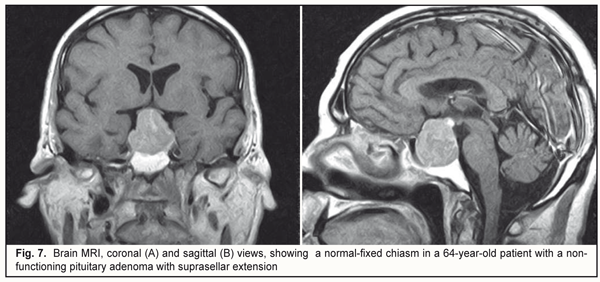

No loss of sensitivity to light was seen in 2 (2%) eyes. Loss of sensitivity to light was classified as mild in 25 (25%) eyes, moderate in 45 (45%) eyes, and severe and very severe in 21 (21%) eyes. The loss was bilateral in 6 (12%) patients. Symmetric chiasmal syndrome was the most common chiasmal syndrome (67%) in our patients with pituitary adenoma with suprasellar extension; this involved reduced visual acuity with symmetric injury to the temporal halves of the visual field secondary to an injury to crossed optic nerve fibers (Fig. 7).